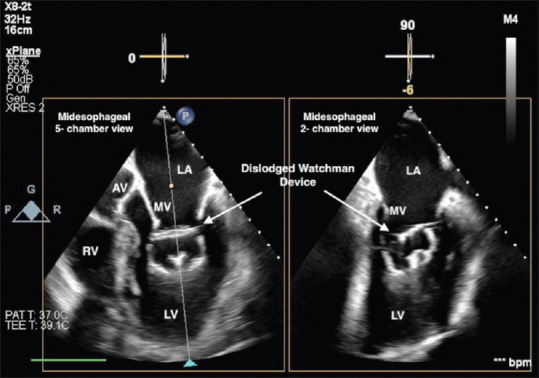

Abstract: WATCHMAN (Boston Scientific, Plymouth, MN, USA) is the most commonly utilized left atrial appendage occlusion device. Although increased operator experience has led to a significant decline in reported complications, serious and potentially fatal events can still occur. We present a case of WATCHMAN device embolization that was identified using transesophageal echocardiography shortly after device deployment, along with the subsequent management and retrieval of the device.